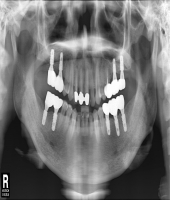

| ● 진료과목 : [임플란트] 치주환자의 보철치료

| ● 내용 : 60대 치주환자의 보철치료 |